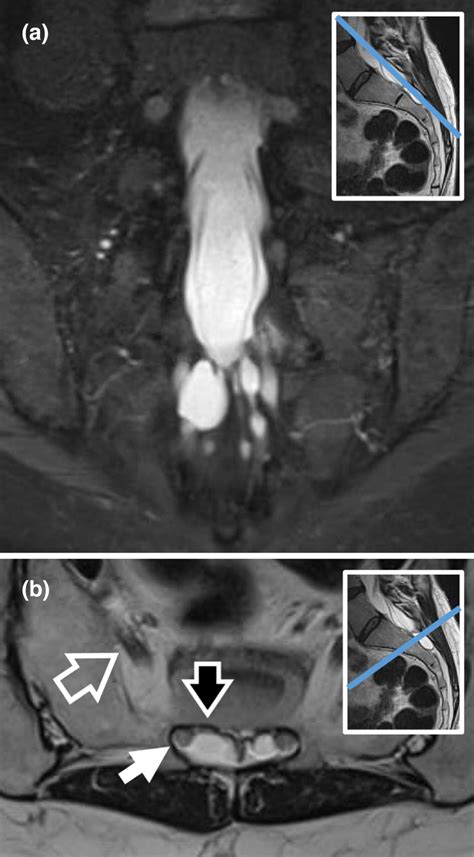

Diagnosing a symptomatic Sacral Tarlov Cyst requires a comprehensive approach. Because they are soft-tissue structures, they are best visualized using high-resolution Magnetic Resonance Imaging (MRI). A radiologist or neurosurgeon will look for specific markers, such as the location, size, and the degree of bone remodeling (erosion) occurring in the sacrum, which indicates that the cyst has been present for a significant period.

In addition to imaging, physicians may conduct a detailed neurological examination to map out sensory deficits and assess muscle strength. Some clinics may also utilize specialized imaging, such as a Cine-MRI, to study the flow of cerebrospinal fluid around the cyst.